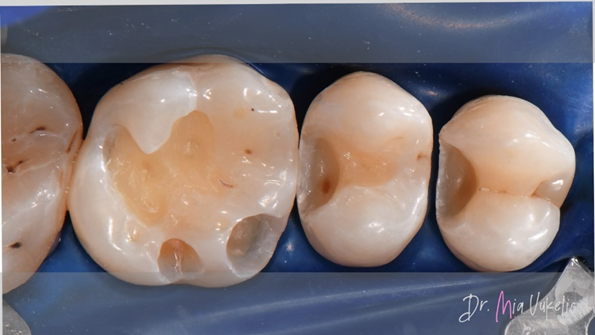

Na goede isolatie met een rubberdam en het plaatsen van wiggen werd de caviteit geprepareerd met een cilindrische boor. Na het verwijderen van de restauratie werd gedemineraliseerd dentine weggehaald met behulp van een stalen boor. Tot slot werden de convergente wanden omgevormd in divergente wanden en werd het inwendige oppervlak van de caviteit gepolijst met diamantpolijstboren.